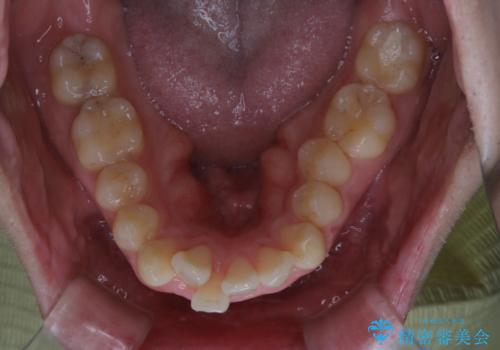

がたつき、口ゴボ(出っ歯)、真ん中のずれを抜歯矯正治療で治す。ワイヤー矯正治療

- 矯正装置

- ワイヤー矯正 審美装置

- 治療計画

- 口元の突出感とがたつきを気にして来院されました。

突出感とがたつきの改善を行うために大きなスペースが必要であったため、親知らず以外の歯を4本歯を抜歯する計画を立てました。

移動量が大きいこと、また、患者さんの生活習慣的にマウスピース装着が難しそうとの理由から

ワイヤー表側矯正装置で治療を行うことになりました。